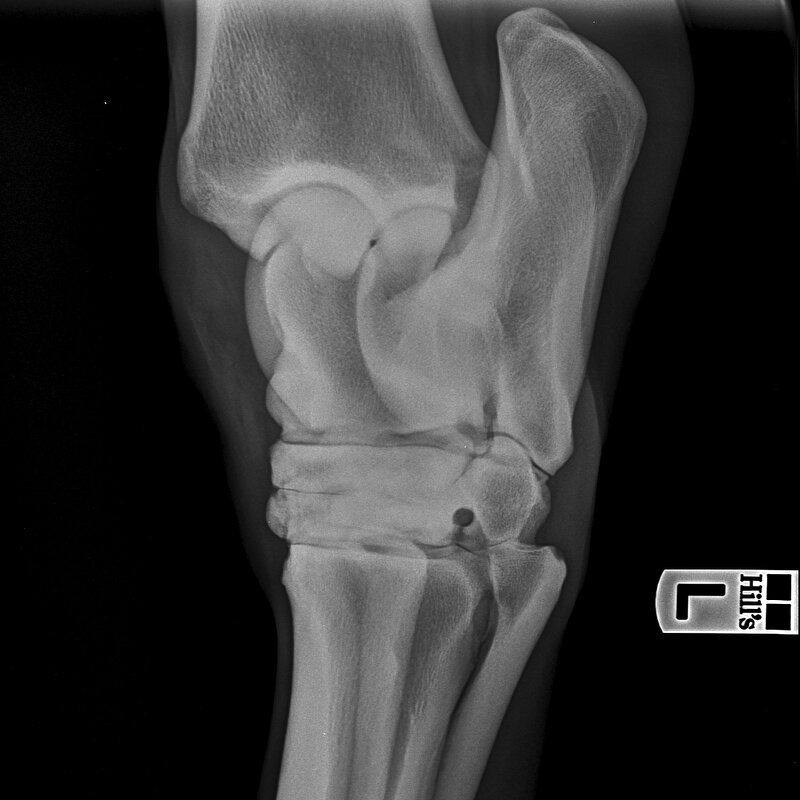

Ik heb een vraagje over röntgenfoto's. Dit gaat over een aard dat we willen kopen.

Het gaat over de sprong links achter dit paard heeft hiervoor een 3 gekregen.

Zelf heb ik geen verstand van foto's en heb ze laten beoordelen door twee artsen de eerste zegt

avulsie fragment in kogel LA in mijn optiek acceptabel beoordeling verhoogd risico.

Voor second opinion tweede arts gevraagd en die zegt ocd niet acceptabel.

Nu weet ik niet zo goed wat te doen heeft iemand ervaring met ocd?

En is het goed te verhelpen als ze er last van krijgen?

Het gaat om een fok merrie van 8 jaar niet bereden, we willen haar zowel voor fokkerij als afstandsritten rijden gebruiken.